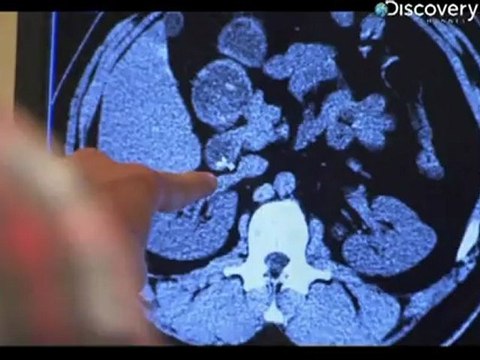

Super-strength appears in almost all comics, whether a natural-born ability or the result of some misguided scientific experiment. This time Daniel investigates four claims of genuine real-life super-strength, in Season 3 Powerlifting Pastor.